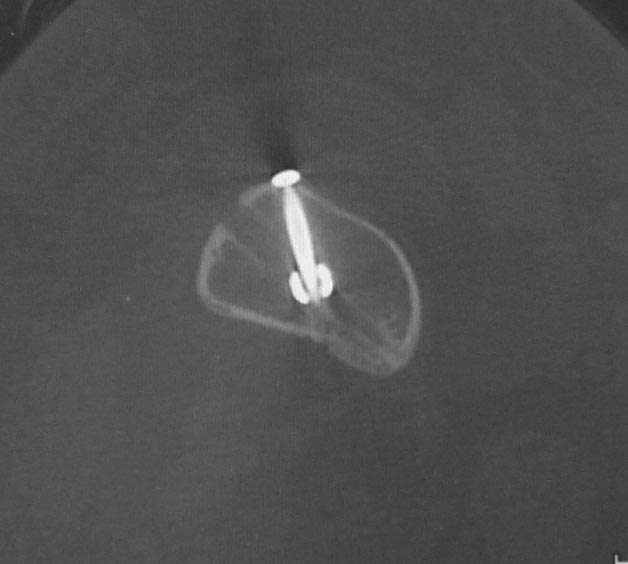

Уважаемые коллеги. Хотелось бы выслушать мнения и советы по представленному случаю. Пациент 42 лет, вес 130 кг, рост около 160 см, сахарный диабет в легкой форме (впервые выявлен после травмы). Травма в феврале 2011 г. - упал с мотоцикла на отдыхе за рубежом. По возвращении в Россию был прооперирован в несколько этапов: в марте 2011 г. - остеосинтез обеих костей правого предплечья пластинами по поводу открытого перелома; интрамедуллярный остеосинтез правого бедра; остеосинтез проксимального конца правой большеберцовой кости. В апреле 2011 г. был доставлен 1 блокирующий винт в дистальное отверстие гвоздя и выполнена пластика крестообразных и наружной боковой связок левого коленного сустава. В феврале 2012 г. были удалены фиксаторы с проксимального конца правой большеберцовой кости и выполнена пластика крестообразных и наружной боковой связок правого коленного сустава. За это время пациент смог начать ходить, сначала с костылями, а затем - без дополнительной опоры. Летом 2013 г. решил укрепить ноги с помощью подъемов пешком на пятый этаж. В результате - усталостная рефрактура правого бедра и перелом интрамедуллярного гвоздя. 09.09.2013 - реостеосинтез латеральным бедренным гвоздем с пластикой костной аутостружкой + СhronoS. Сейчас, через 6 мес после операции, может ходить без дополнительной опоры, периодически беспокоит болезненность в области правого бедра. На сегодняшних КТ - отсутствие признаков консолидации. Нужно ли что то делать и, если да, то что? Рассматриваемые варианты: повторная костная пластика дефекта; доставить блокирующие винты (самый проксимальный винт был удален через 3 мес после операции). Еще раз менять гвоздь не хотелось бы. На представленных снимках: бедро в 2011 г., через несколько мес после операции; в 2012 г., на стадии консолидации; со сломанным гвоздем; сразу после повторной операции (3 рентгенограммы). Все КТ - сегодняшние. Заранее спасибо за ответы.

ждать-не ждать? Срочности нет, подождать можно, но активно, т.е. оценить клиническую и рентгенологическую динамику: два месяца назад, сейчас и еще через пару месяцев. Уменьшатся боли, появится более убедительная мозоль - ждите и наблюдайте дальше. Отсутствие положительной динамики можно приравнять к отрицательной динамике. Очевидно, что здесь имеют место быть обе проблемы: биологическая -мозоль слабая и механическая - тонкий гвоздь, недостаточная стабильность. Тогда -удаление, рассверливание (очень аккуратное, по 0.5 мм шаг, острыми фрезами, чтобы не пожечь кость - кортикал толстый и довольно прочный). Для 130 кг диаметр гвоздя минимум 12 мм, лучше больше. Здесь можно и 14мм гвоздь взять и блокировать дистально винтами 6,0 мм. Открывать перелом и пытаться делать еще пластику экстрамедуллярно не стоит. Рассверливания будет достаточно.

Согласен, стержень тонковат в дистальном отломке. Если совсем никак не возможно перепровести с рассверливанием более толстый стержень, можно согласиться с вашим предложением ввести еще один винт в дистальный конец гвоздя, но полностью убрать винты из проксимального отломка, чтобы перенести осевую нагрузку на кость и не опасаться перелома гвоздя или винтов.

Насколько это эффективно в отношении консолидации будет видно примерно через 6 недель. Незабудьте сделать, если его нет, обычный свежий снимок до динамизации для последующего сравнения.

Источник проблем - отсуствие рассверливания, тонкий гвоздь и костная пластика. При интрамедуллярном остеосинтезе (относительная стабильность) класть кусочки кости открыто бесполезно - не приживут. Только еще ухудшили кровоснабжение концов. А что там с длиной сегмента? Если длина не потерялась - реостеосинтез с рассверливанием, как А.Семенистый написал. Если укорочение - удалить, остеотомия на другом уровне и дистракиця, на стыке - компрессия, и по достижении нужной длины - заштифтовать с рассверливанием, аппарат снять только после запирания гвоздя.

Боли в области ложного сустава подтверждают, что ожидания не помогут и приведут к повторному перелому интрамедуллярного гвоздя. Стандартная процедура - рассверливание и толстый гвоздь в динамике. Нагрузка с первых дней.